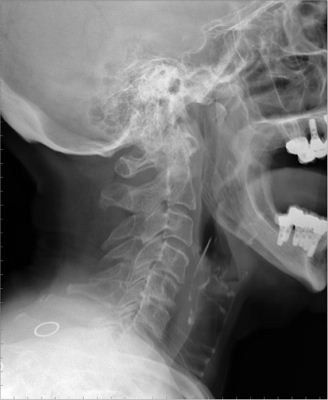

Artrosis cervical.

Artrosis cervical

APR Cervicoartrosis